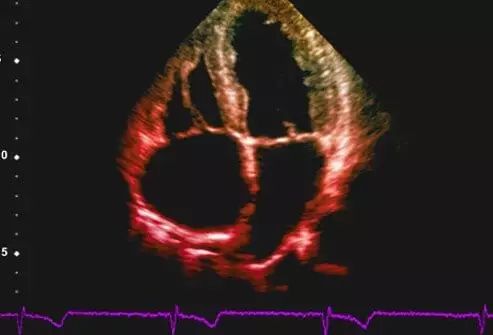

5.超声心动图

超声心动图是利用超声的特殊物理学特性实时检查心脏和大血管的解剖结构及功能状态的一种首选无创性技术,可观察心脏各个腔室和瓣膜的运动特征。临床常用的有三种:M型、二维和多普勒超声心动图。此外还有实时三维超声心动图、各种负荷超声心动图(包括运动和药物诱发)、经食道超声心动图、声学造影及组织多普勒等。